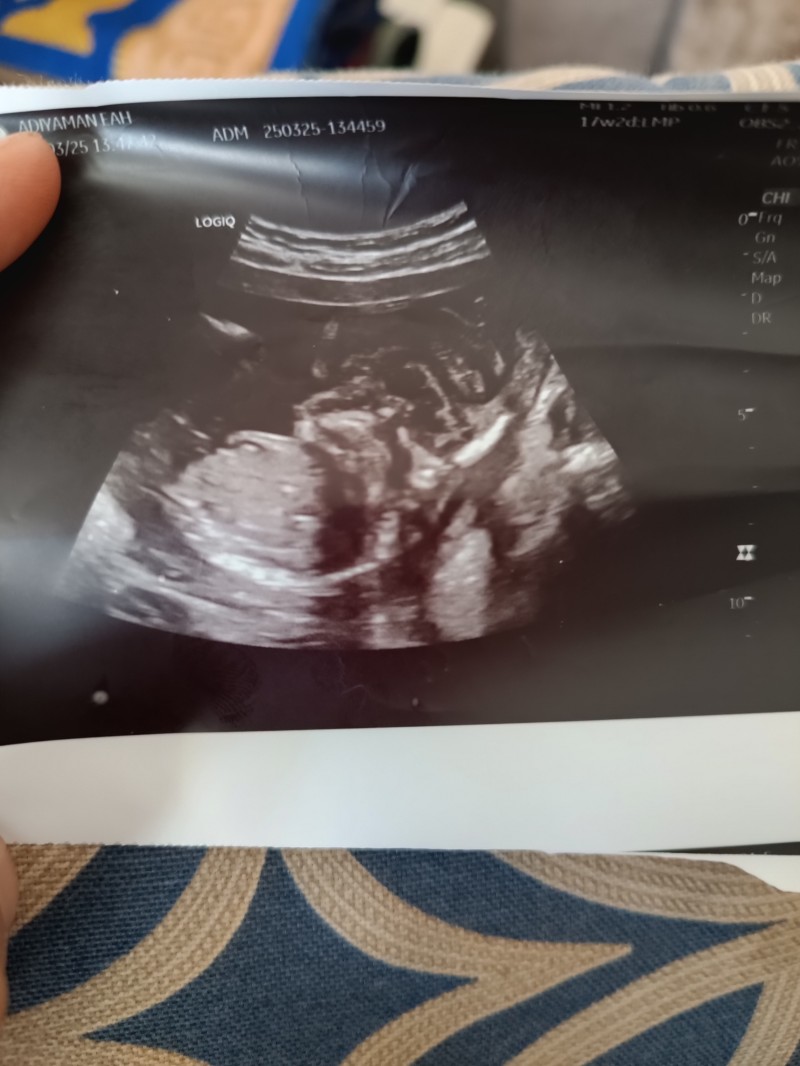

Bir önceki ultrason kağıdında var

image

(795 puan) tarafından

Erkek.....